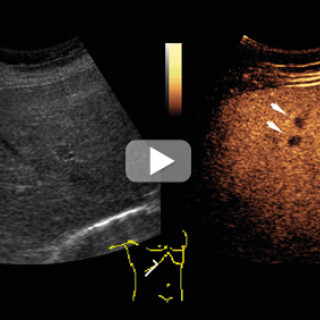

En mann i 20-årene ble innlagt med hodepine, svimmelhet, oppkast, slapphet og vekttap. Cerebral MR-undersøkelse viste diffuse, konfluerende forandringer i hvit substans, forenlig med cerebral vaskulitt. Konvensjonell angiografi med selektiv injeksjon i begge karotider og a. vertebralis høyre side viste normale arterier uten kalibervekslinger eller okklusjoner. Prøver fra spinalvæsken viste økt antall mononukleære celler, overveiende modne lymfocytter, med 107 leukocytter per kubikkmillimeter (≤ 5 leukocytter per mm³) og økt mengde totalprotein 0,94 g/l (0,10 – 0,40 g/l). Øyeundersøkelse viste...